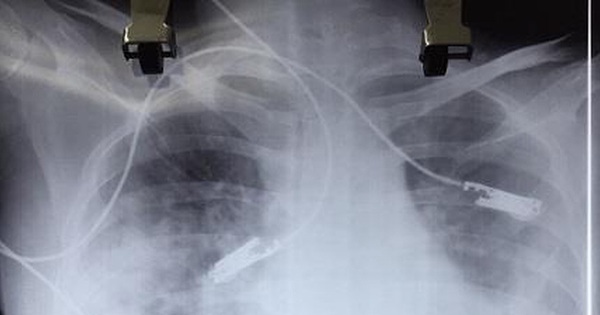

Do tình trạng chuyển biến nặng, bệnh nhân được chuyển tới khoa cấp cứu Bệnh viện Bạch Mai trong tình trạng sốt, suy đa phủ tạng, hôn mê, xuất huyết não, có tổn thương phổi, hình ảnh phim chụp có tổn thương tim.